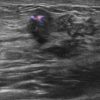

Ung thư vú

» Thông tin: Nữ giới – 25 tuổi.

» Lâm sàng: Khối tuyến vú.